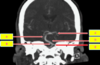

Label 5, 6 & 7

1 - superior temporal gyrus;

2 - inferior frontal gyrus; 3 - insular cortex;

4 - temporal stem;

5 - internal capsule;

6 - thalamus;

7 - lentiform nucleus (the internal and external globus pallidus and the putamen)

8 - frontal horn;

9 - superior circular sulcus;

10 - inferior circular sulcus.

1 - superior temporal gyrus; 2 - inferior frontal gyrus; 3 - insular cortex; 4 - temporal stem; **5 - internal capsule;** **6 - thalamus;** **7 - lentiform nucleus** (the internal and external globus pallidus and the putamen) 8 - frontal horn; 9 - superior circular sulcus; 10 - inferior circular sulcus.